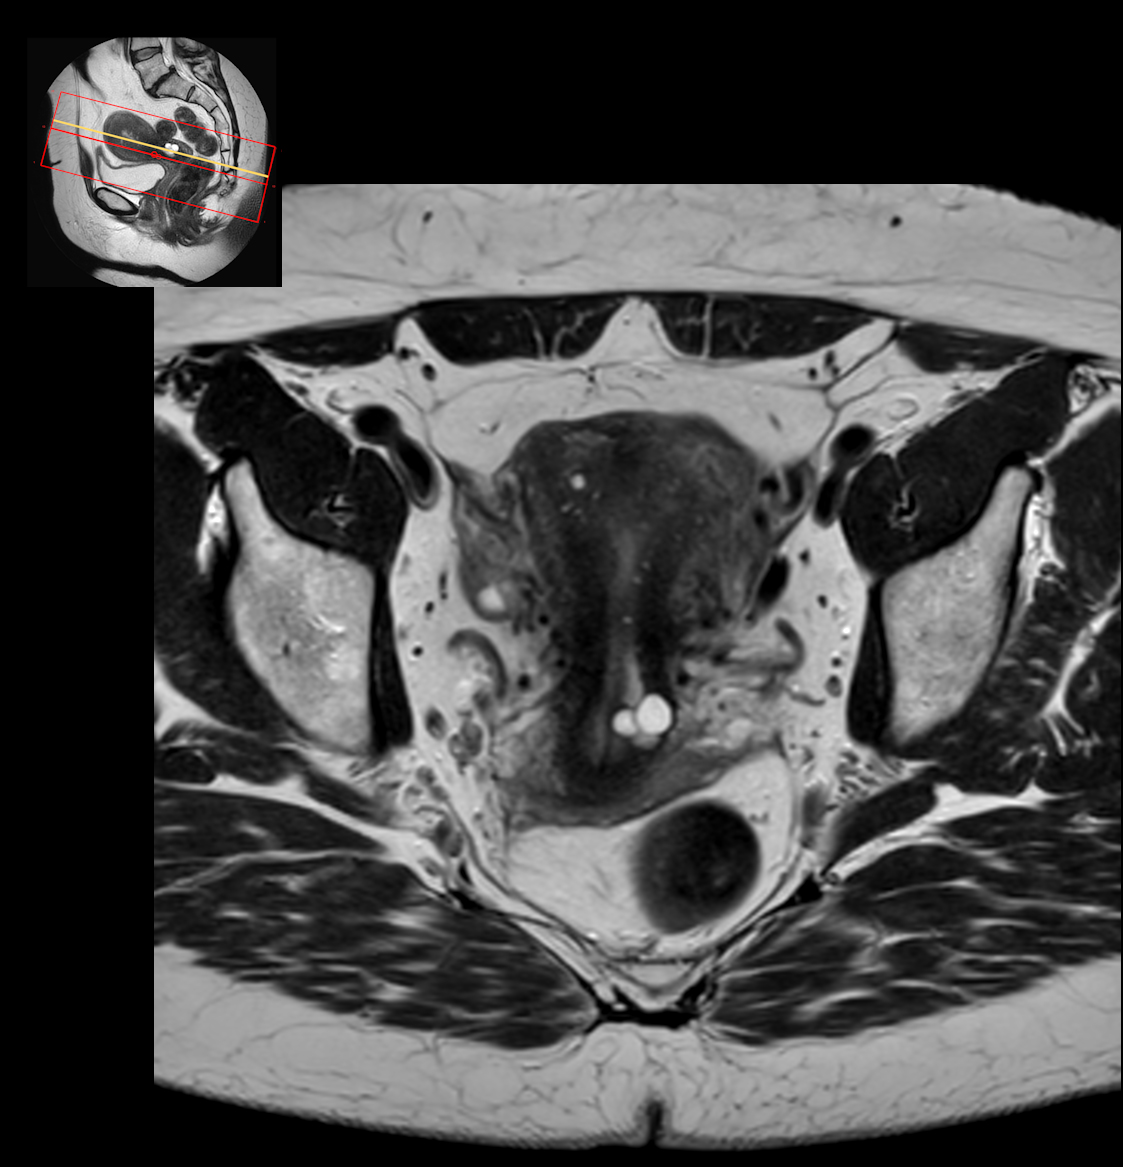

Axial T2w SPAIR